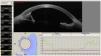

The iridocorneal angle, due to its implications in the physiopathology of aqueous humour drainage, is a fundamental structure of the anterior chamber. Anterior segment optical coherence tomography (AS−OCT) is a rapid and non-invasive technique that obtains images in vivo. The high resolution allows it to analyse the normal anatomy of the angle, any alterations, and the changes that occur after different therapeutic interventions. AS−OCT technology has evolved to provide images that allow the identification and quantification of the angular structures in healthy subjects and in glaucoma patients, and especially the trabecular meshwork and the Schlemm's canal. It also enables the angle width to be quantified, with some objective parameters that have been standardised in recent years, such as the trabecular-iris angle (TIA), the angle opening distance (AOD), and the trabecular-iris area (TISA). This technique has multiple uses in the study of the different mechanisms of angle closure, the evaluation of changes after a laser peripheral iridotomy or iridoplasty after cataract surgery, as well as after the implantation of phakic lenses.

El ángulo iridocorneal por sus implicaciones en la fisiopatología del drenaje del humor acuoso es una estructura fundamental de la cámara anterior. La tomografía de coherencia óptica de segmento anterior (OCT-SA) es una técnica rápida y no invasiva que obtiene imágenes de los tejidos vivos con una alta resolución permitiendo conocer la anatomía normal del ángulo, sus alteraciones y los cambios que se producen en el mismo tras diferentes intervenciones terapéuticas. La tecnología de la OCT-SA ha ido evolucionando hasta ofrecer imágenes que permiten identificar y cuantificar estructuras angulares claves en sujetos sanos y en pacientes con glaucoma, especialmente la malla trabecular y el canal de Schlemm, lo que puede contribuir a ampliar el conocimiento de la fisiopatología del glaucoma. Además, permite cuantificar la abertura angular con unos parámetros objetivos descritos en los últimos años, entre los que destacan el ángulo irido-trabecular (TIA), la distancia de abertura angular (AOD) y el área irido-trabecular (TISA). La OCT-SA presenta múltiples utilidades en el estudio de los distintos mecanismos del cierre angular, la evaluación de los cambios angulares tras la realización de una iridotomía láser o iridoplastia, cirugía de la catarata o el implante de lentes fáquicas.